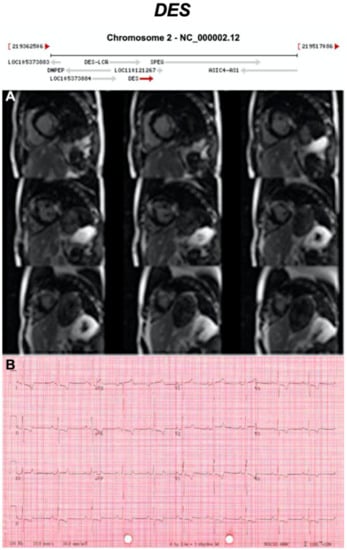

| DES | Cytoplasmic Intermediate Filament | <1% | AD | LV, BIV | ARVC7 | 2q35; 9 | Myofibrillar myopathy, DCM | Moderate for ARVC |

3.2.3. Desmin (DES) (Encoded by DES)

- Bermúdez-Jiménez, F.J.; Carriel, V.; Brodehl, A.; Alaminos, M.; Campos, A.; Schirmer, I.; Milting, H.; Abril, B.Á.; Álvarez, M.; López-Fernández, S.; et al. Novel desmin mutation p.Glu401Asp impairs filament formation, disrupts cell membrane integrity, and causes severe arrhythmogenic left ventricular cardiomyopathy/dysplasia. Circulation 2018, 137, 1595–1610. [Google Scholar] [CrossRef]

- Strach, K.; Sommer, T.; Grohé, C.; Meyer, C.; Fischer, D.; Walter, M.C.; Vorgerd, M.; Reilich, P.; Bär, H.; Reimann, J.; et al. Clinical, genetic, and cardiac magnetic resonance imaging findings in primary desminopathies. Neuromuscul. Disord. NMD 2008, 18, 475–482. [Google Scholar] [CrossRef] [PubMed]